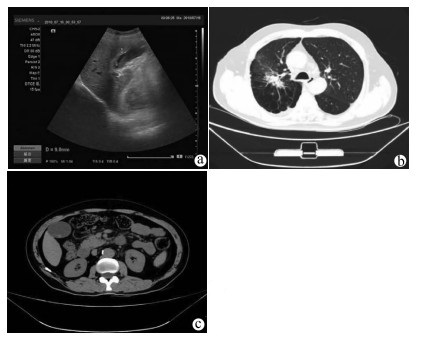

Gallbladder metastasis from lung adenocarcinoma: A case report

Jie ZHANG, Qianping QU, Hong LI, Shaohua ZHANG, He HUANG, Fugui LI

2021, 37(8): 1919-1920. DOI: 10.3969/j.issn.1001-5256.2021.08.037

Abstract(1323) HTML (837) PDF (2844KB)(44)

Abstract: